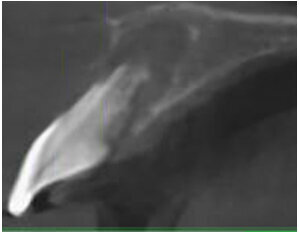

Wymienione metody mają swoje ograniczenia, które należy rozważyć w każdej sytuacji przed przystąpieniem do zabiegu. W przypadku własnym, m.in. ze względu na istniejący już ubytek kostny i wiek pacjenta nie było możliwości przeprowadzenia zabiegu implantacji natychmiastowej, gdyż wiązałoby się to z brakiem uzyskania stabilizacji pierwotnej implantów, a co najważniejsze zatrzymaniem wzrostu otaczającej wszczep kości.7 Zabiegi z zakresu augmentacji zębodołu poekstrakcyjnego z wykorzystaniem materiałów kościozastępczych spowodowałoby również ograniczenie wzrostu wyrostka zębodołowego, a ze względu na wielkość ubytku kostnego utworzenie niepełnowartościowej kości, słabo unaczynionej, co skutkowałoby brakiem osteointegracji implantu wszczepionego po zakończeniu wzrostu kostnego pacjenta. Z kolei zaniechanie wszelkiego postępowania leczniczego spowodowałoby znaczny ubytek kości z prawdopodobnym wpuklaniem kanału nerwu przysiecznego w to miejsce (Ryc. 13). W konsekwencji pacjent obarczony byłby koniecznością przeprowadzenia wielu zabiegów z zakresu chirurgii regeneracyjnej wyrostka zębodołowego.

Ryc. 13_Kanał nerwu przysiecznego.